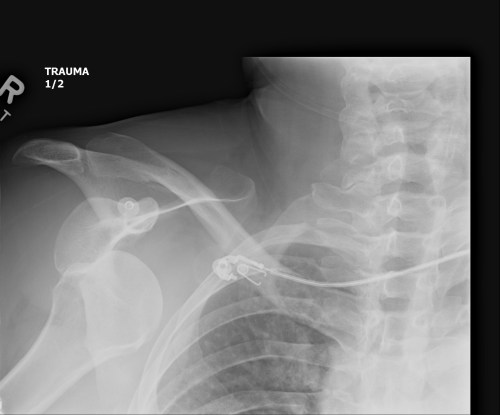

It has been almost three months since my last post here, and things have fallen quiet on our sister blog Anatomy to You, too. I thought it was time for an update, which is mostly a summary of stuff we’ve been doing on my team, but also featuring some interesting images if you stick around. The relative silence here has partly been due to me giving myself some nice holiday time w/family in L.A., then having surgery to fix my right shoulder, then recovering from that and some complications (still underway, but the fact that I am doing this post is itself evidence of recovery).

Stomach-Churning Rating: 4/10; semi-gruesome x-rays of me and hippo bits at the end, but just bones really.

X-ray of my right shoulder from frontal view, unlabelled

Labelled x-ray

Nonetheless, as welfare science likes to term it, it’s entirely “a life worth living”. I have to pick my battles more than I used to, and I’ve had to learn to take more time to get exercise, rest, and avoid the stresses (or even unpleasant people) that can cause my health to take rapid downward spirals. I’m more fragile in many ways, such as having to stop doing karate because my shoulders have weakened. Here’s some interesting anatomy for you from a recent MRI scan of my right shoulder:

My left shoulder in top cross-sectional view, with the missing parts of my humeral head crudely outlined in red. There's more amiss here, too.

My left shoulder in top cross-sectional view, with the missing parts of my humeral head crudely outlined in red. There’s more amiss here, too.

My seizures cause my shoulder flexors to spasm, raising my arms up and crushing my humerus against my glenoid cavity of my scapula and causing occasional dislocations that abrade the humerus against the rim of the glenoid. The result, after numerous seizures, has been the wearing away of the articular cartilage of my shoulder and then the crumbling of the bony head of my humerus. Thus, once my NHS surgeon is ready to in coming months, I am due to have my coracoid process of my scapula cut off and moved, with its attached muscles and ligaments, to be screwed into the front of my glenoid cavity, bracing my humeral head more tightly against the glenoid and thereby resisting future dislocations. Luckily that operation can be done with several small incisions and endoscopy; invasive as the surgery is; thus recovery time won’t be so long.

Latarjet surgery (view of right shoulder joint [glenoid] from front): coracoid process moved posteroventrally. More details (w/videos) here.

It amuses me that all of this intense surgery looming on the horizon doesn’t worry me. I just want it done. I’ve been through a comparable surgery with my left shoulder, involving screwing my greater tuberosity back onto my humerus, so I know what recovery is like, and now that shoulder is doing fine. All that aside, my physical integrity has declined and I feel it every day. I may never return to my karate classes and earn that black belt I was seeking as a life-goal, but time will tell. I am trying to do what I can to remain as strong as I can for as long as I can.